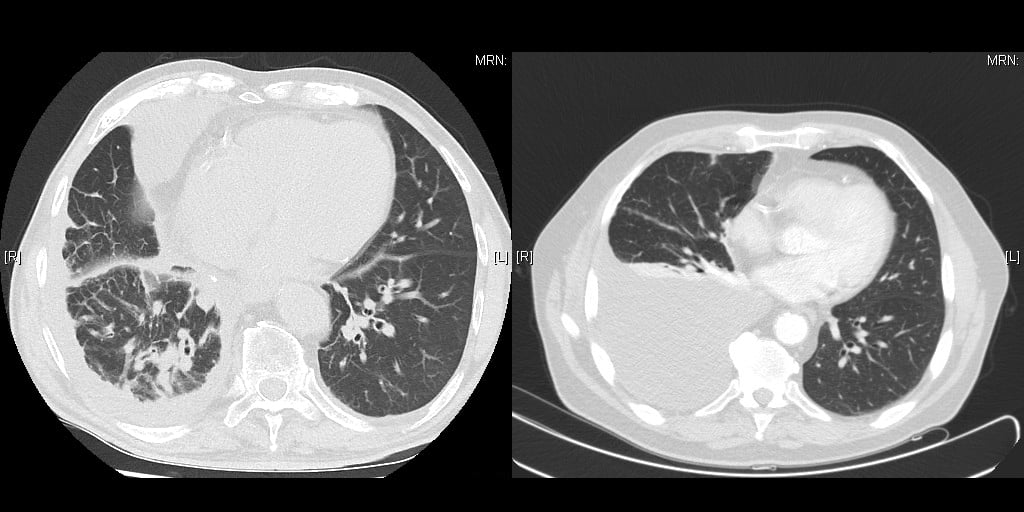

Abb. 2: Links: Schlechte Indikation für Lokalanästhesie: Der rechte Hemithorax ist geschrumpft, die Pleura parietalis verschwartet, es gibt keinen Erguss. Es ist mit schweren Verwachsungen zu rechnen. Rechts: Gute Indikation für Lokalanästhesie, reichlich Erguss, die Lunge ist von der Brustwand abgehoben.